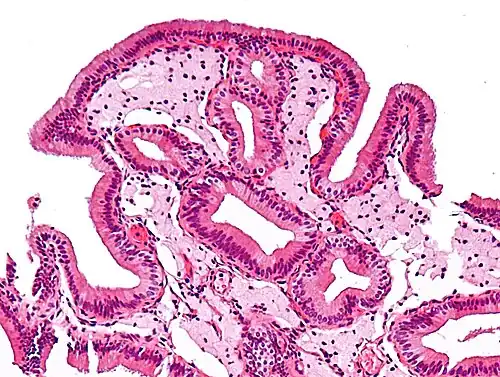

| Micrograph of cholesterolosis of the gallbladder, a very common gallbladder disease. Cholecystectomy specimen. H&E stain. | |